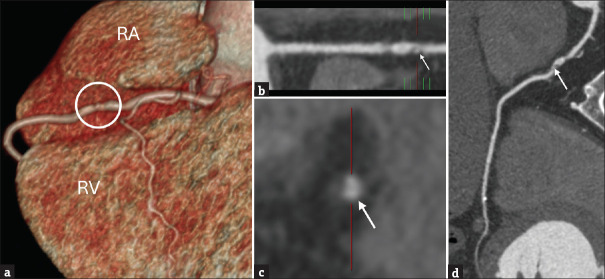

Cardiac computed tomography (CT) has evolved significantly as a critical tool in diagnosing and managing cardiac diseases, greatly facilitated by technological advancements in multidetector systems, dose-reduction techniques, and sophisticated imaging algorithms. This article discusses the historical progression and technological evolution in cardiac CT (CCT), focusing on the impact of 64-multidetector row CT and dual-energy CT systems on improving spatial and temporal resolutions and reducing radiation exposure. It explores the role of these technologies in enhancing diagnostic accuracy, such as through detailed three-dimensional reconstructions and minimized imaging artifacts. Furthermore, it highlights the integration of machine learning to automate complex imaging analysis and photon-counting CT, which promises higher resolution and further dose reduction. Prospective studies and ongoing trials such as FASTTRACK coronary artery bypass grafting also underscore the potential of advanced CT technologies in refining procedural planning and execution. The continuous advancements in detector technology, computational techniques, and image reconstruction are poised to expand the applications and efficacy of CCT, cementing its role in modern cardiology.